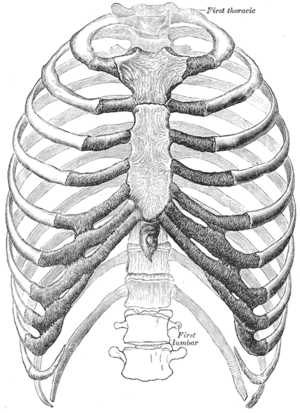

The human rib cage (Source: Gray's Anatomy of the Human Body, 20th ed. 1918) | |

In vertebrate anatomy, ribs (Latin: costae) are the long curved bones which form the rib cage. In most tetrapods, ribs surround the chest, enabling the lungs to expand and thus facilitate breathing by expanding the chest cavity. They serve to protect the lungs, heart, and other internal organs of the thorax. In some animals, especially snakes, ribs may provide support and protection for the entire body.

Human anatomy

Humans have 24 ribs (12 pairs). The first seven sets of ribs, known as "true ribs" (costae verae) also known as vertebrosternal ribs, are directly attached to the sternum through the costal cartilage. Rib 1 is unique and harder to distinguish than other ribs. It is a short, flat, C-shaped bone. The vertebral attachment can be found just below the neck and the majority of this bone can be found above the level of the clavicle. Ribs 2 through 7 have a more traditional appearance and become longer and less curved as they progress downwards.[1] The following five sets are known as "false ribs" (costae spuriae), three of these sharing a common cartilaginous connection to the sternum, while the last two (eleventh and twelfth ribs) are termed floating ribs (costae fluctuantes) or vertebral ribs. They are attached to the vertebrae only, and not to the sternum or cartilage coming off of the sternum. Some people lack one of the two pairs of floating ribs, while others have a third pair.

In general, human ribs increase in length from ribs 1 through 7 and decrease in length again through rib 12. Along with this change in size, the ribs become progressively oblique (slanted) from ribs 1 through 9, then less slanted through rib 12.[1]

The ribcage is separated from the lower abdomen by the thoracic diaphragm which controls breathing. When the diaphragm contracts, the thoracic cavity is expanded, reducing intra-thoracic pressure and drawing air into the lungs. This happens through one of two actions (or a mix of the two): when the lower ribs the diaphragm connects to are stabilized by muscles and the central tendon is mobile, when the muscle contracts the central tendon is drawn down, compressing the cavity underneath and expanding the thoracic cavity downward. When the central tendon is stabilized and the lower ribs are mobile, a contraction of the diaphragm elevates the ribs, which works in conjunction with other muscles to expand the thoracic indent upward.